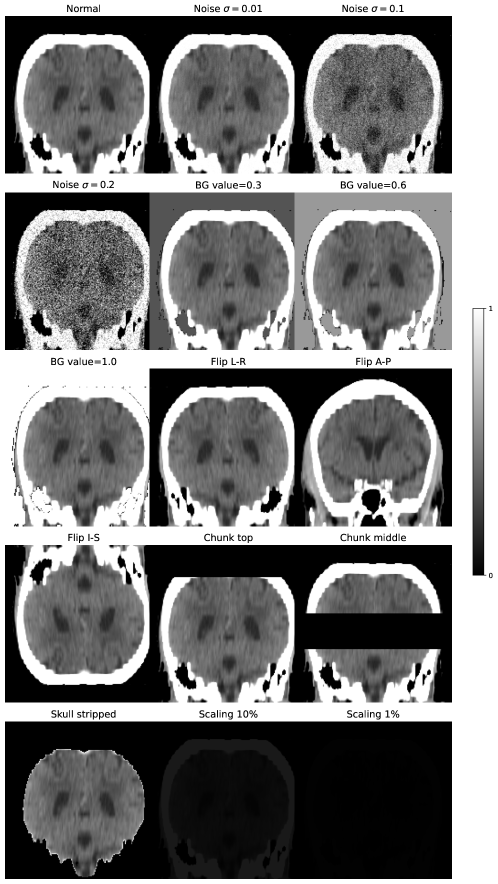

The KCH dataset was used for algorithm validation. It consists of 47 clinical scans selected for the presence of ICH, all with ground-truth masks provided by an experienced neuroradiologist. This dataset was used to represent in-distribution test data; it was further used to produce a set of corrupted scans to test our algorithms in the near-OOD setting. A range of corruptions were applied to each scan in the dataset, designed to emulate a number of scenarios such as imaging artefact, image header errors, and errors in the preprocessing pipeline that is typically applied before data is input into a network. The corruptions included: addition of Gaussian noise, inversion through each of the three image planes, skull-stripping, setting the image background to values not equal to 0, global scaling of all image intensities by a fixed factor, and the deletion of a set of slices (or chunks) of the image. Any spatial manipulations of the image were also applied to the labels. This totalled 15 corruptions applied to each image, creating a corrupted dataset of 705 images. Examples of the corruptions applied are included in Appendix A.

Appendix A Demonstration of image corruptions

fig:corruptions_demo